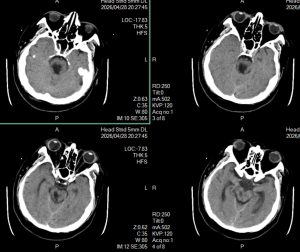

2026年4月29日 Home立体定向技术脑干出血急诊穿刺引流,抢救生命 脑干出血急诊穿刺引流,抢救生命 By admin 立体定向技术 0 Comments 病人1,4月13日急性脑干出血,迅速神志不清 术前CT显示脑干出血 脑干出血发病时 手术计划 术后复查,显示定位准确,穿刺道完全符合术前计划 术后7天,血肿基本引流干净 手术后15天情况 现病人生命体征平稳,正在促醒康复中 About Author admin Add a Comment 取消回复您的邮箱地址不会被公开。 必填项已用 * 标注Comment:*Name:* Email Address:* Website: Save my name, email, and website in this browser for the next time I comment. Δ